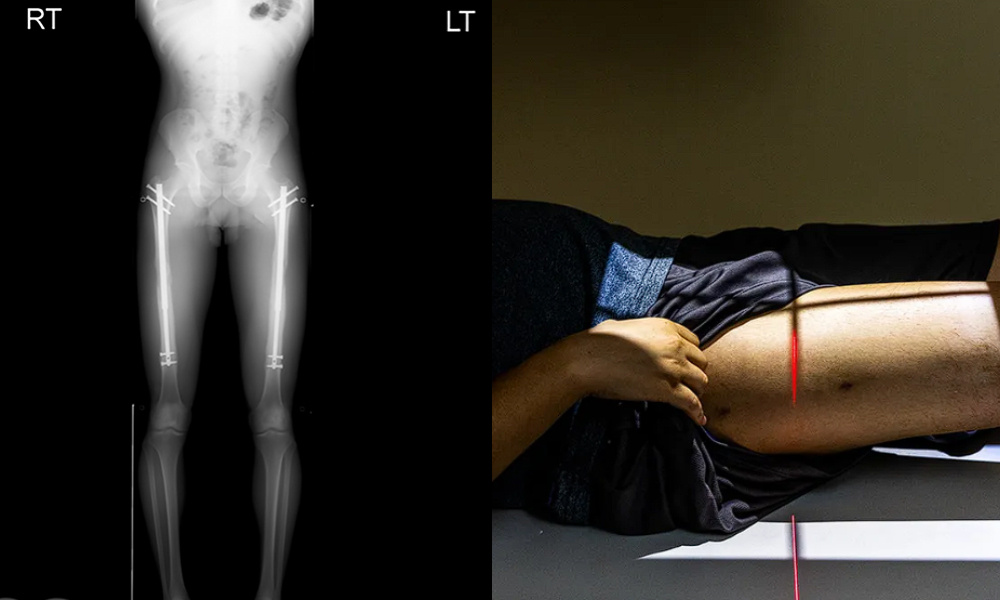

图源:GQ

断骨断骨,顾名思义就是把股骨或胫骨切断,然后把可调节的金属钉插进去。

这个既灵活又坚固的玩意儿,可以通过遥控器调节长度。

整个拉伸过程大概90天,整整三个月时间里,接受断骨增高的人都得面临着“拉伸”带来的痛苦。

毕竟拉伸的不仅有骨头,还有周围的腿筋和神经组织。

反正止痛药真的得随时必备,否则那种疼痛会让人终生难忘。